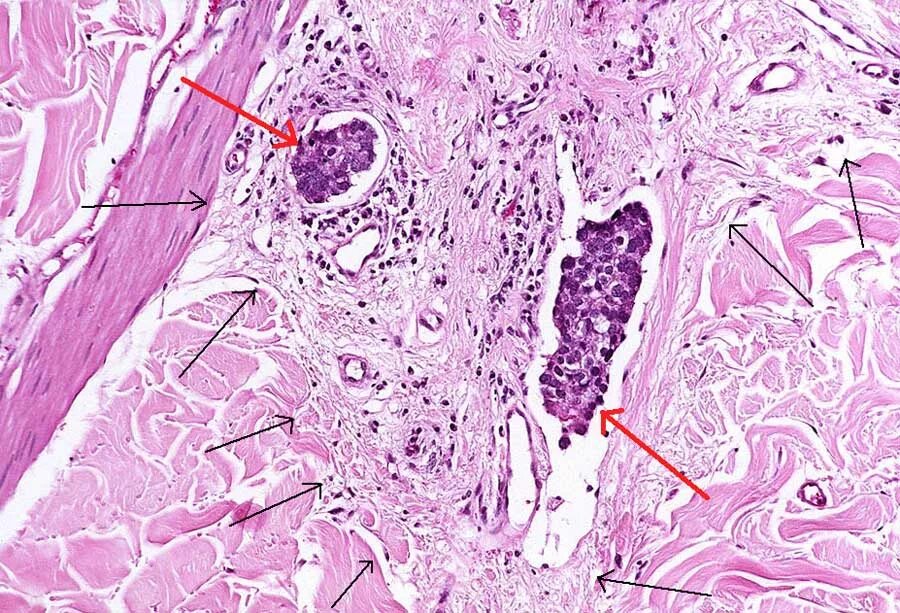

Метастазы в лимфоузлах молочной железы